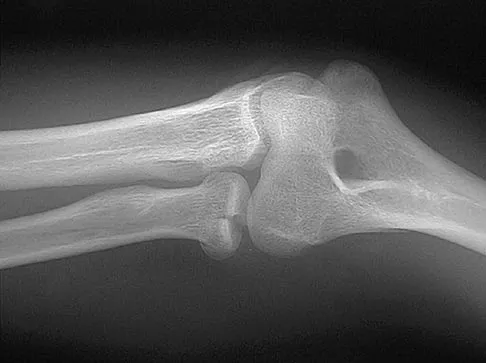

Figure 2 shows the radiograph of a 26-year-old auto mechanic who injured his right dominant elbow in a fall during a motocross race. Examination reveals pain and catching that limits his range of motion to 45 degrees of supination and 20 degrees of pronation. The interosseous space and distal radioulnar joint are stable. Management should consist of

Explanation

The radial head is an important secondary stabilizer of the elbow, helping to resist valgus forces. There has been a movement toward open reduction and internal fixation of the radial head when technically feasible, especially in a relatively high-demand athlete or laborer. The examination and radiograph suggest that displacement of the fragment is great enough to create a mechanical block. Extended splinting would only serve to encourage arthrofibrosis. Early range of motion is appropriate if there is minimal displacement of the radial head fragement, it is stable, and there is no mechanical block to motion. Fragments larger than one third of the joint surface should be excised only if it is not possible to reduce and repair the fragment. Primary excision of the radial head should be avoided if possible. Complications after excision of the radial head include muscle weakness, wrist pain, valgus elbow instability, heterotopic ossification, and arthritis. Hotchkiss RN: Displaced fractures of the radial head: Internal fixation or excision? J Am Acad Orthop Surg 1997;5:1-10.